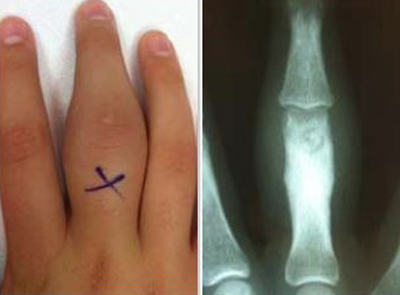

photo and x-ray of an osteoid osteoma

(Left) Photo shows swelling of the proximal finger from an osteoid osteoma. The X is over the nidus (center) of the tumor. (Right) An X-ray of the tumor shows thickened bone around the nidus, a characteristic feature of an osteoid osteoma.

Reproduced from Julka A, Jebson P, Tomaino M: Common benign tumors of the hand. Orthopaedic Knowledge Online Journal 2015; 13(8)1. Accessed August 2019.